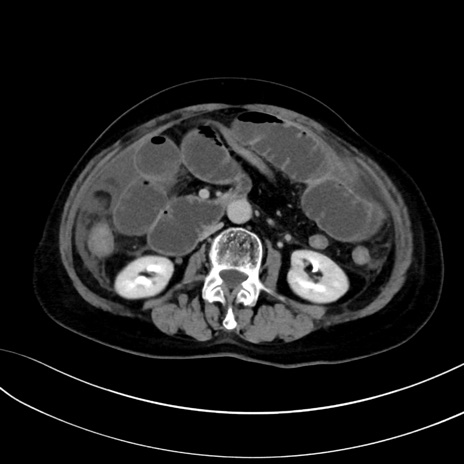

(冠状断像)1日半後